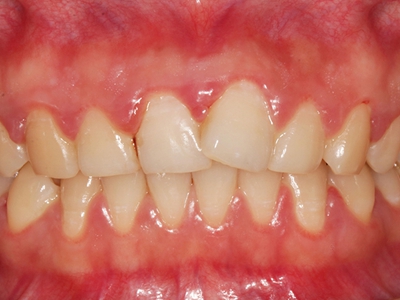

慢性龈炎又称边缘性龈炎或单纯性龈炎,主要表现为游离龈和龈乳头因炎性水肿,而变为鲜红或暗红色,龈缘变厚,龈乳头圆钝肥大。慢性龈炎的患病率高,治愈后仍可复发,部分患者可发展成为牙周炎。

慢性龈炎的病损部位一般局限于游离龈和龈乳头,以前牙区为主,尤其以下前牙区最为显著,患者常因刷牙或咬硬物时牙龈出血而就诊。游离龈和龈乳头颜色变为鲜红或暗红色,病变较重时炎性充血可波及附着龈。龈缘变厚,龈乳头圆钝肥大,可增生呈球状,覆盖牙面。牙龈松软脆弱,缺乏弹性。

当牙龈以增生性反应为主时,龈缘和龈乳头呈坚韧的实质性肥大,质地较硬而有弹性。龈沟液量增多,还可能出现龈沟溢脓现象。